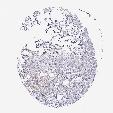

CANCER BREAST CANCER Show tissue menu

BRCA TCGA BRCA VALIDATION PROTEIN EXPRESSION